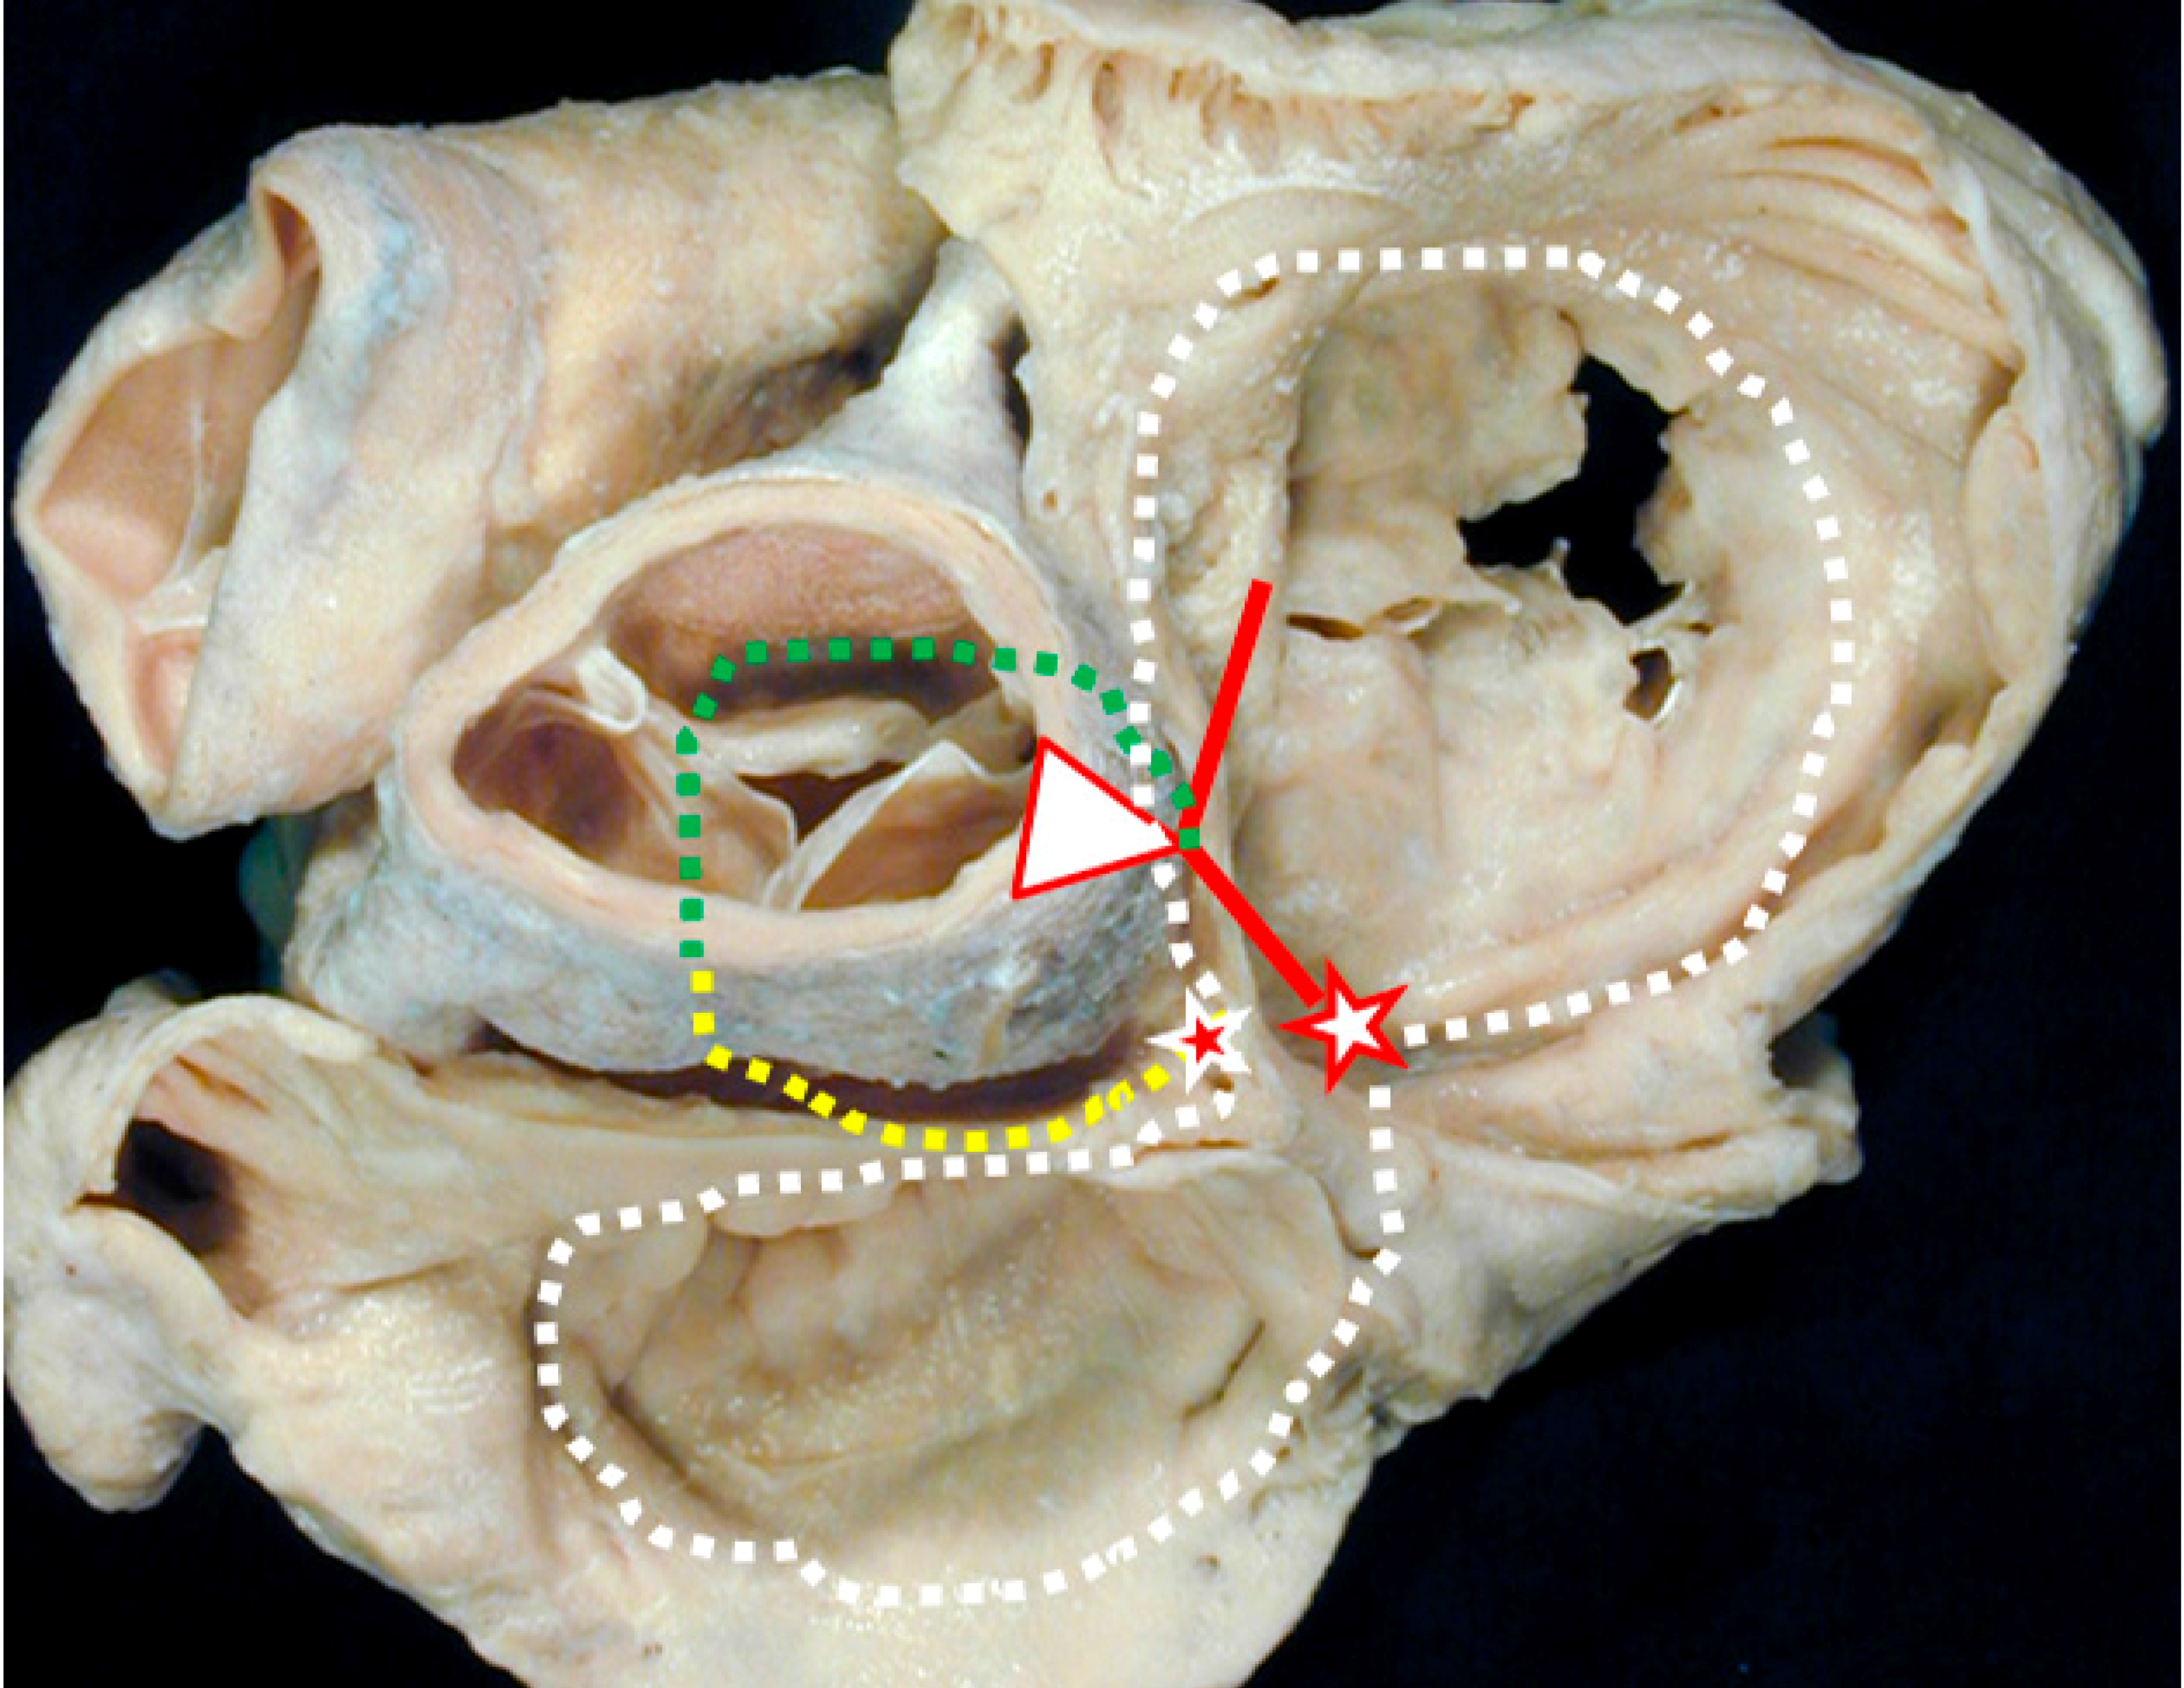

- McGuire, M.A.; de Bakker, J.M.; Vermeulen, J.T.; Opthof, T.; Becker, A.E.; Janse, M.J. Origin and significance of double potentials near the atrioventricular node. Correlation of extracellular potentials, intracellular potentials, and histology. Circulation 1994, 89, 2351–2360. [Google Scholar] [CrossRef] [PubMed]

- McGuire, M.A.; de Bakker, J.M.; Vermeulen, J.T.; Moorman, A.F.; Loh, P.; Thibault, B.; Vermeulen, J.L.; Becker, A.E.; Janse, M.J. Atrioventricular junctional tissue. Discrepancy between histological and electrophysiological characteristics. Circulation 1996, 94, 571–577. [Google Scholar] [CrossRef] [PubMed]